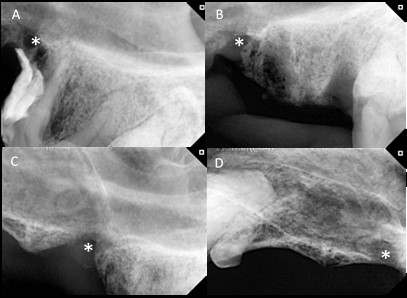

A los 3 y 9 meses de haberle dado el alta, el paciente fue intervenido nuevamente ya que se le diagnosticó una estomatitis ulcerativa crónica canina, la cual implicaba realizar nuevas exodoncias. Aprovechando estas instancias se realizaron radiografías de control de la cirugía en la pieza 108. En dichas radiografías se visualizó una remodelación ósea favorable, no se observaron indicios radiográficos de osteomielitis (figura 4).

Figura 4: Radiografías correspondientes al caso 2. A: En la radiografía se visualizan restos de resina radiopacos sobre las raíces mesiales de la pieza 208 y pérdida ósea adyacente a los restos de resina (*). A su vez presenta disminución de la radiodensidad ósea del hueso alveolar entre las raíces mesiales y la distal. También se observa una discontinuidad en la tabla ósea compatible con fístula oronasal. B: Radiografía inmediata a la exodoncia de la pieza 208 y extracción de la resina. Se visualizan los espacios correspondientes a los alvéolos dentales vacíos y la rarefacción ósea con disminución de radiodensidad craneal a los alvéolos dentales compatible con osteomielitis (*). C: Radiografía correspondiente a la zona de la pieza 208, 3 meses luego de realizada la exodoncia y colocación de PRF, se observa una remodelación ósea con aumento de la radiodensidad ósea en la zona correspondiente al alvéolo de las raíces mesiales y en la zona correspondiente al defecto óseo generado por la resina (*). D: Radiografía a los 9 meses de la exodoncia y aplicación de PRF. Presenta una buena radiodensidad a nivel óseo en la zona correspondiente al defecto (*). Tomada del Servicio de Odontoestomatología de la Facultad de Veterinaria, Udelar.

En el caso 2 realizamos radiografías de control a los 3 y 9 meses, se observó una remodelación ósea positiva y un aumento de la radiodensidad del hueso alveolar afectado. Existen estudios previos en perros con enfermedad periodontal que utilizaron PRF en defectos alveolares posextracción dental de una hemiarcada, mientras que en la otra hemiarcada realizaron la exodoncia de otras piezas dentales, pero sin colocación de PRF, lo que sirve de control dentro del propio individuo (Tambella et al., 2020). Estos autores analizaron mediante software la densidad ósea al día de la cirugía y a las 3 semanas de evolución y observaron un aumento de densidad significativo en el grupo tratado con PRF, aunque no así en el grupo control. A su vez, realizaron estudios histopatológicos y observaron una reducción del score inflamatorio y un aumento de la vascularización en los grupos tratados con PRF. Por otro lado, en un estudio experimental que utilizó perros beagle se realizaron exodoncias con colocación de PRF y sin colocación de PRF (To et al., 2019). Posteriormente se obtuvieron muestras para histopatología y se evaluó la formación ósea, se observó un mayor rango de formación al día 14 y 30. El mismo estudio encontró un aumento de osteopontina y osteocalcina, dos marcadores de formación ósea, a los 30 días en el grupo PRF con respecto al grupo control, lo cual indicaría un aumento de la actividad osteoblástica en el grupo tratado con PRF. Cabe mencionar que los estudios experimentales presentan limitaciones ya que no reflejan la complejidad de las enfermedades que ocurren naturalmente en un paciente. Si bien en nuestro estudio realizamos los controles radiográficos en tiempos diferentes y no realizamos análisis cuantitativo, nuestros resultados muestran un aumento de la densidad ósea a nivel radiográfico, lo que coincide con los estudios mencionados.